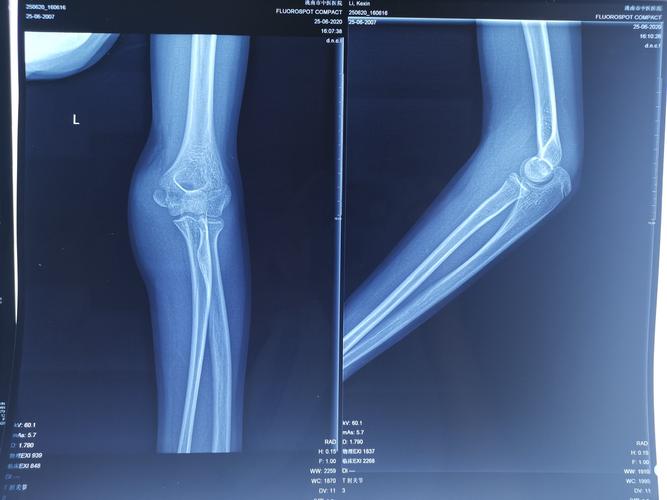

术后石膏固定35天,现患者左侧肘关节活动受限,关节活动度伸-屈:45-135

肘关节正侧位片图片